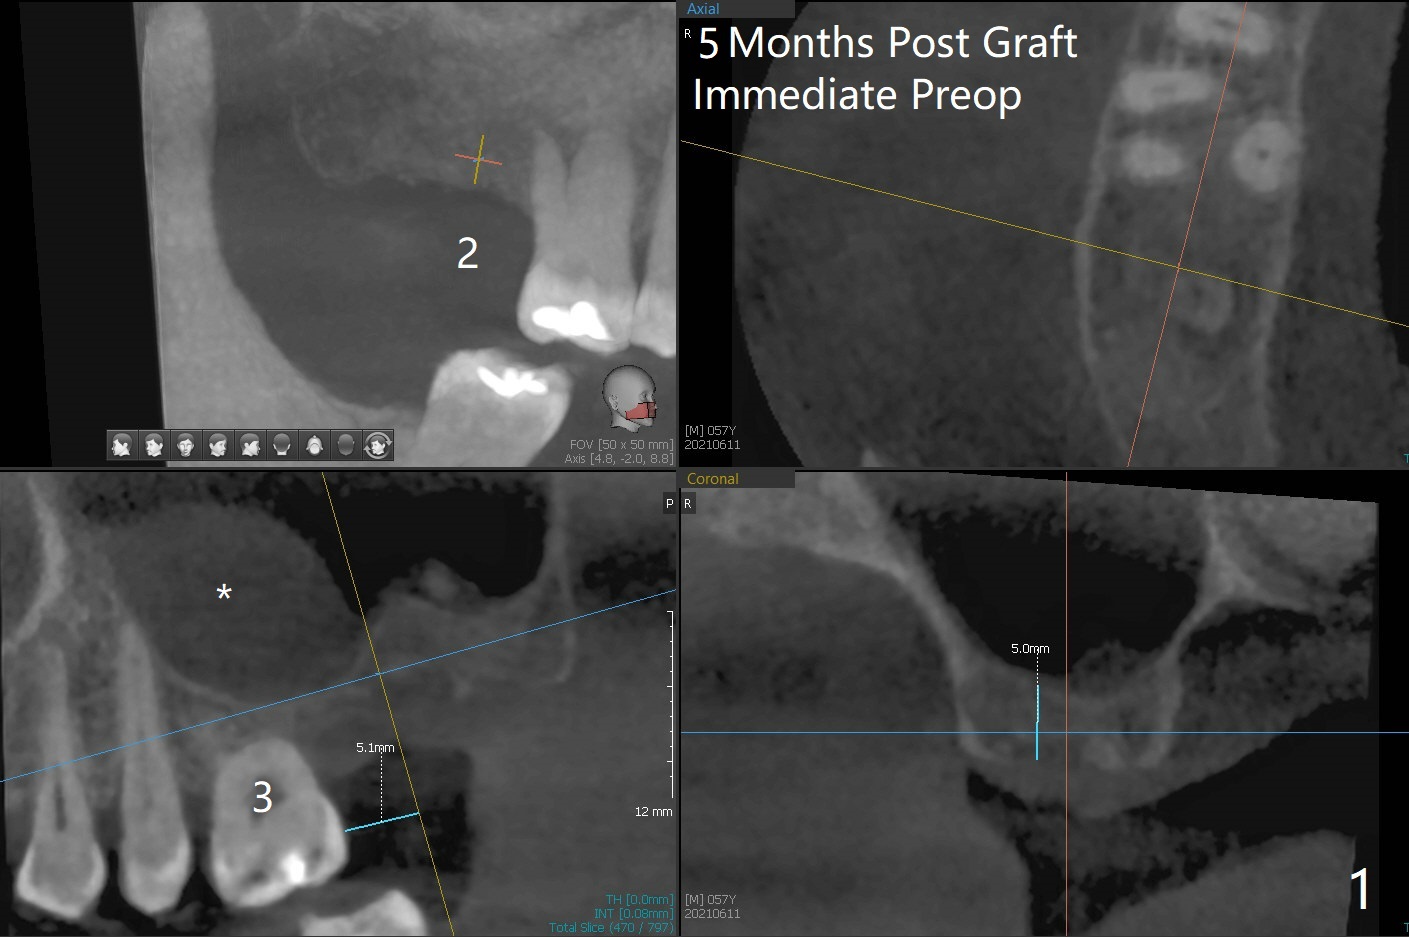

尽管事先准备15号刀片,看到完整2号牙牙槽嵴就舍不得切开。放置以前导板(用于即种),用软组织环形刀做个记号,接着用活检环形刀切取钻洞表面软组织,保存于PRF液体中。术前CT显示3号牙上方粘液囊肿(图一:*),而2号牙上方窦膜薄,总之两者都不好惹(容易感染,窦膜破),提升需要特别小心。完成初步钻洞后,使用17-19毫米长的DIO圆钻,放置粘性骨粉,使用4.5x10毫米报废植体进行提升(到第一横线),结果窦底没有穿(图二:红箭头)。接着使用尖头钻头从原来2.2x5.3毫米一直到3.5x10毫米,几乎每使用一个钻头后都检查窦底完整性,再放置骨粉,使用4.0x10毫米植体提升(到第二横线),好像穿过窦底(图三)。再加骨粉,使用4.5x10毫米植体扭力底,最后放置PRF膜,很难塞入上颌窦,结果只能从钻洞上端近中很小裂口塞入,植入5x8.5毫米正式植体(图四),上颌窦里骨粉呈蘑菇状(*)。临床检查腭侧(P)植体牙槽嵴下,其余骨壁难于判断。而咬翼片却显示植体颊侧(B),腭侧均在牙槽嵴下(图五)。为了减少术后骨质吸收,放置愈合螺帽后(图六:S),植体表面添加骨粉(*),最终把保存的软组织放回原位(二期手术:减少上颌窦与口腔交通,感染),牙周胶水粘固(图七)。术后没有鼻出血。